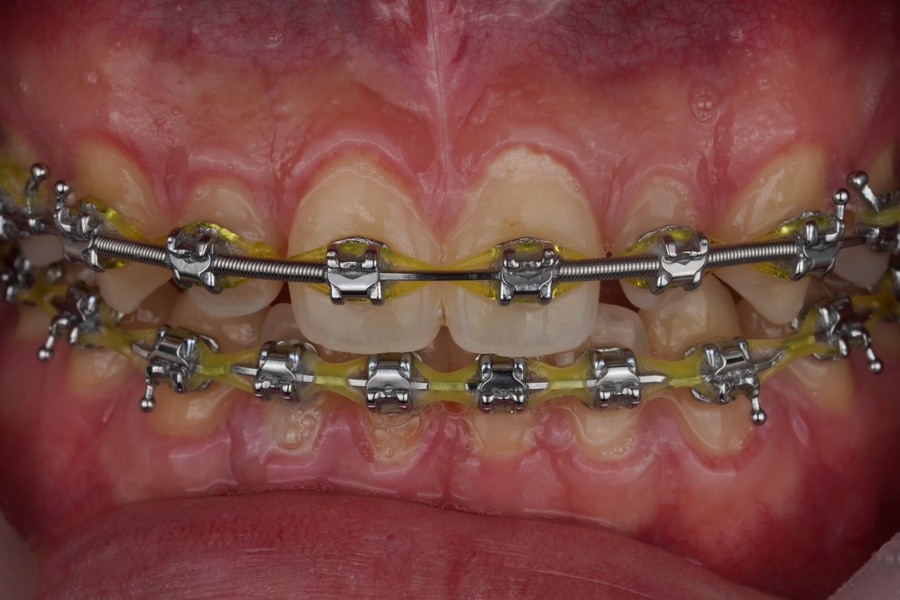

출처 아카이브 열기한달 전, 교정기를 낀 분이 찾아오셨습니다.

가지런해진 치아에 어울리지 않는

왜소치가 양쪽에 있었는데,

그런 경우

교정 마무리 할 때 라미네이트나

크라운 치료를 보통 추천받게 되죠.

처음 오셨을 때 사진

위에 올려둔 사진은

한달 전 사진입니다.

교정 마무리 중에 오셔서

진단을 먼저 받고 가셨어요.